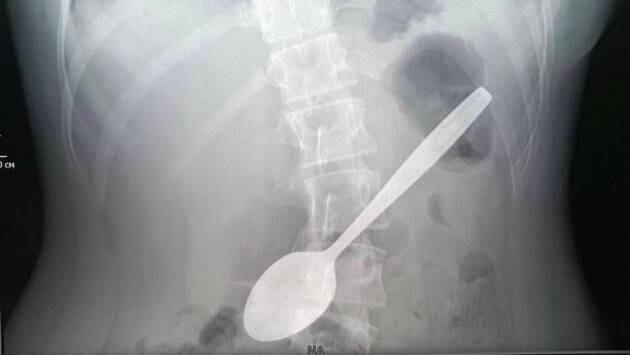

Подмосковные врачи достали из желудка школьницы 15-сантиметровую ложку

Врачи Детского клинического центра имени Л. М. Рошаля извлекли из желудка девочки ложку длиной 15 сантиметров, которой она пыталась достать застрявший в горле кусок яблока. Об этом в понедельник, 5 мая, рассказали в Минздраве Московской области.

В ведомстве отметили, что длительное нахождение металлического предмета в желудке может вызвать серьезные осложнения, такие как пролежень, перфорация стенки или непроходимость, но в данном случае ложка не успела причинить вреда.

Сообщается, что операция длилась около часа и прошла успешно. Сейчас девочка чувствует себя хорошо и уже выписана домой.

Юная леди пыталась ею достать кусок яблока, который застрял у нее в горле, и случайно проглотила, — передает Telegram-канал министерства.